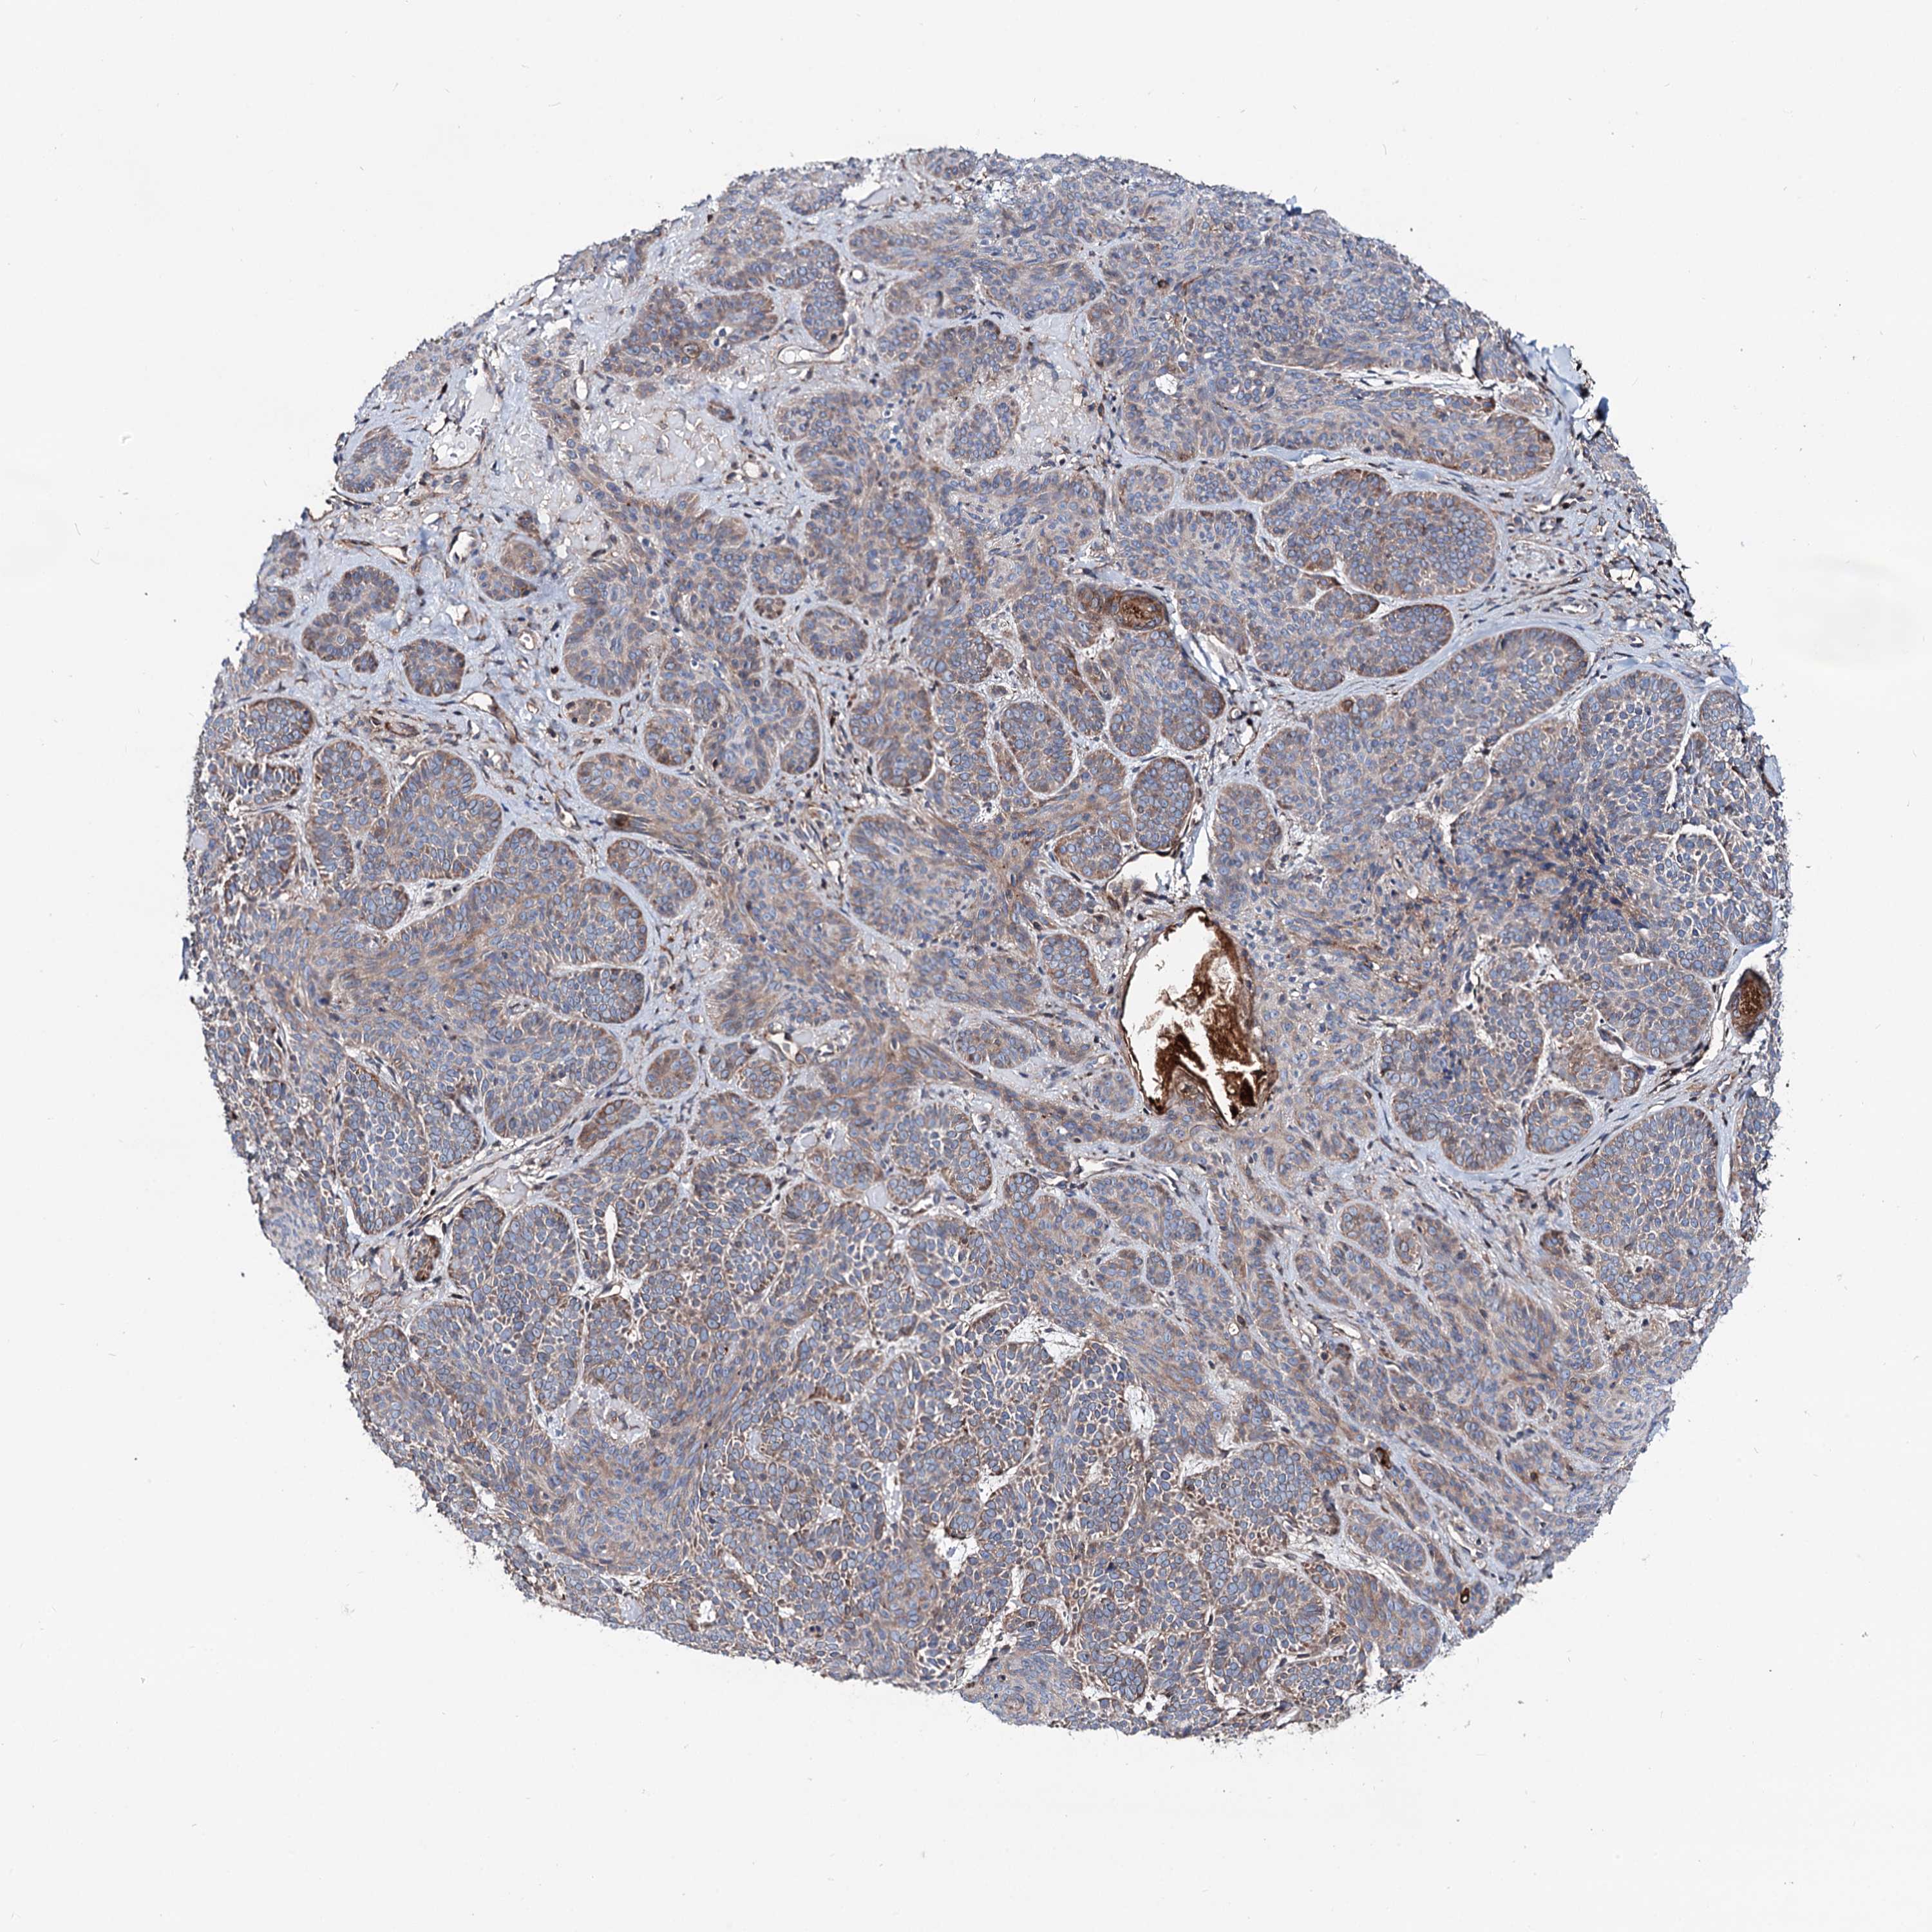

Basal cell and squamous cell cancer

SKIN CANCER - Protein expressioni

A mouse-over function shows sample information and annotation data. Click on an image to view it in a full screen mode. Samples can be filtered based on level of antibody staining by selecting one or several of the following categories: high, medium, low and not detected. The assay and annotation is described here.

Each image is clickable and will lead to virtual microscopy that enables deeper exploration of all samples and also displays staining intensity scores, fraction scores and subcellular localization as well as patient and tissue information for each sample.

Antibody HPA038929

Squamous cell carcinoma, NOS